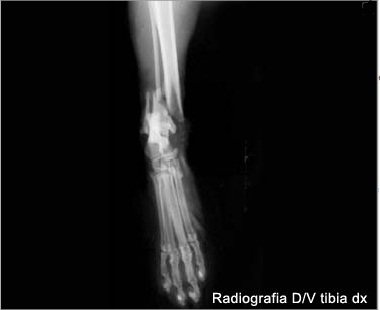

Frattura di femore che si ricompone con mezzo di fissità interno.

Biondi, dvm 1 1 ospedale veterinario gregorio vii, roma, italia. La frattura al femore può essere: .non conoscendo il mondo dei veterinari non so se una pratica diffusa operate una frattura con un fissatore esterno.poi anche le dimensioni di un femore di un gatto sono molto piccole.magari con un fissatore pediatrico o uno per mano. Difficilmente, invece, la zampa viene amputata: Queste fratture sono di solito il risultato di trauma, ma possono essere causate da malattie. Frattura atraumatica dell'epifisi della testa del femore nel gatto. I vostri elaborati > casi clinici. Classificate in base alla sede anatomica. Qual è la terapia più adatta? Il trattamento di una frattura del femore richiede quasi sempre l'intervento di sintesi chirurgica. Frattura comminuta femore distale intercondiloidea. La frattura del femore è un evento particolarmente grave che colpisce in modo schiacciante gli anziani dai 70 anni in su. Quali sono gli esercizi e quando si possono fare? Un'anziana ha riportato la frattura del femore dopo essere caduta questa mattina intorno alle 12 a la donna stava dando da mangiare ad alcuni gatti randagi quando ha perso l'equilibrio ed è caduta. Leggi la voce frattura del femore sul dizionario della salute. Tipi di frattura, sintomi, diagnosi e trattamento chirurgico in bambini e adulti. La frattura del femore si verifica più comunemente in persone giovani e negli anziani.